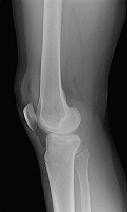

Figures 1 through 3 are the radiographs of a 25-year-old man who is brought to the emergency department after a motorcycle collision. He is complaining of isolated knee pain. Examination reveals swelling, popliteal ecchymosis, joint line pain, and limited knee joint motion. His pulses and sensation are normal.

This knee injury is best described as a